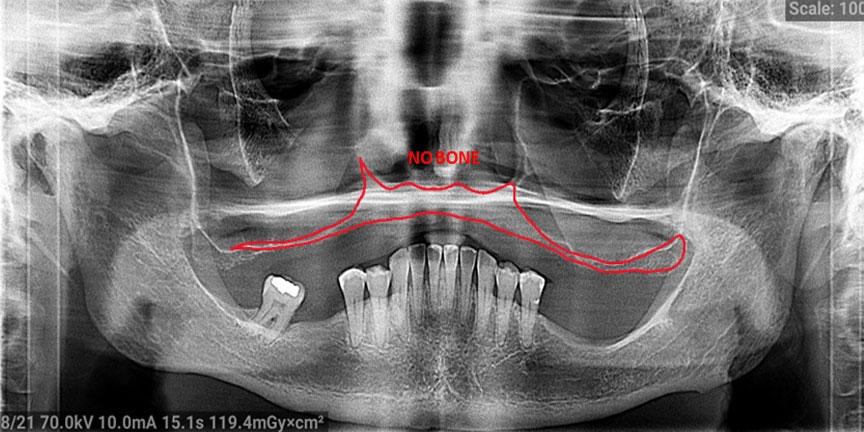

Difficult Cases

- We treat patients when other providers cannot manage.

Severe Bone Loss